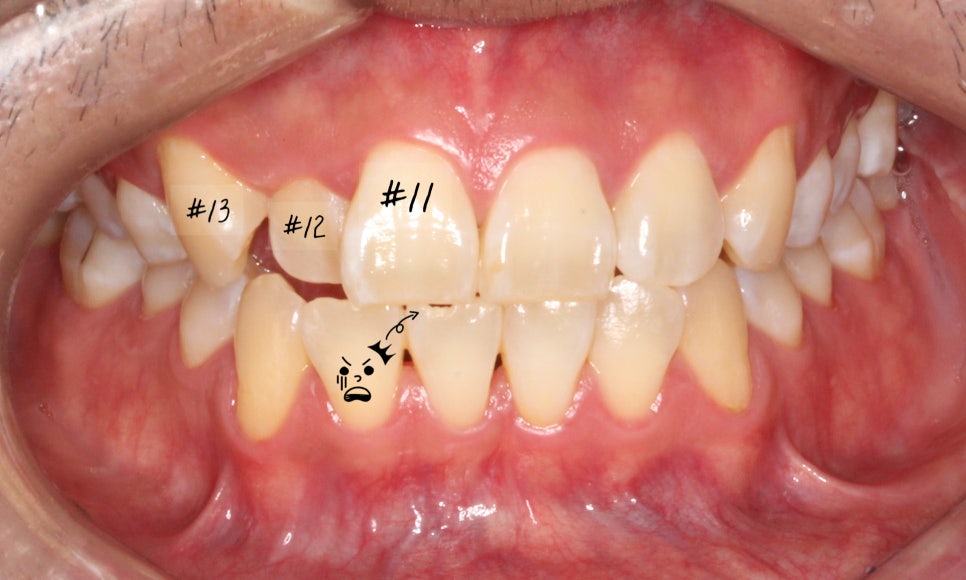

이번에는 덧니 고민으로 오신 환자분인데요.

윗니 오른쪽 두 번째 앞니가 들어가 있고,

다른 앞니끼리도 너무

세게 닿아서 고민이라고 오셨어요.

사진을 보실 땐

눈에 보이는 방향의 왼쪽이

환자에게는 오른쪽입니다.

첫 방문 때 이렇게 아래 앞니도 깨져있고,

#12 치아는 안으로 들어가 있었습니다.

환자분은 #13 이 튀어나왔다고 생각하시던데,

이렇게 씹는 면 사진으로 보면

#13이 튀어나왔다라기보단

#12가 상대적으로 들어가 있는 게 맞죠.